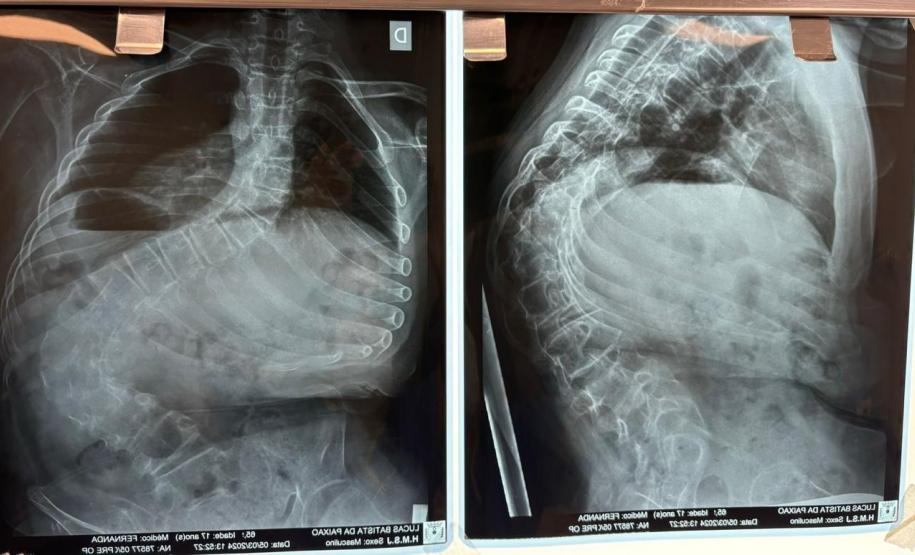

Aos 14 anos, a adolescente Milena de Andrade Carvalho, moradora de Guaratuba, no Litoral do Estado, foi diagnosticada com escoliose idiopática. Sem causa definida, esse tipo de escoliose pode surgir a partir dos quatro anos até a adolescência e ocorre durante o estirão de crescimento. Quando a condição da curvatura ultrapassa os 40 graus, a escoliose se torna progressiva e o paciente continua entortando. Essa condição ocorre com maior frequência em meninas e é muito importante que os pais estejam atentos a qualquer sinal do problema.

“Descobrimos a escoliose por acaso, nunca tínhamos percebido a deformidade, até que um dia ao amarrar meu biquíni, minha mãe observou que eu estava com a coluna torta e ao passar a mão percebeu a curvatura. Decidimos então procurar atendimento médico e tive o diagnóstico da doença já com 50 graus de curvatura e indicação imediata de cirurgia”, contou a adolescente.